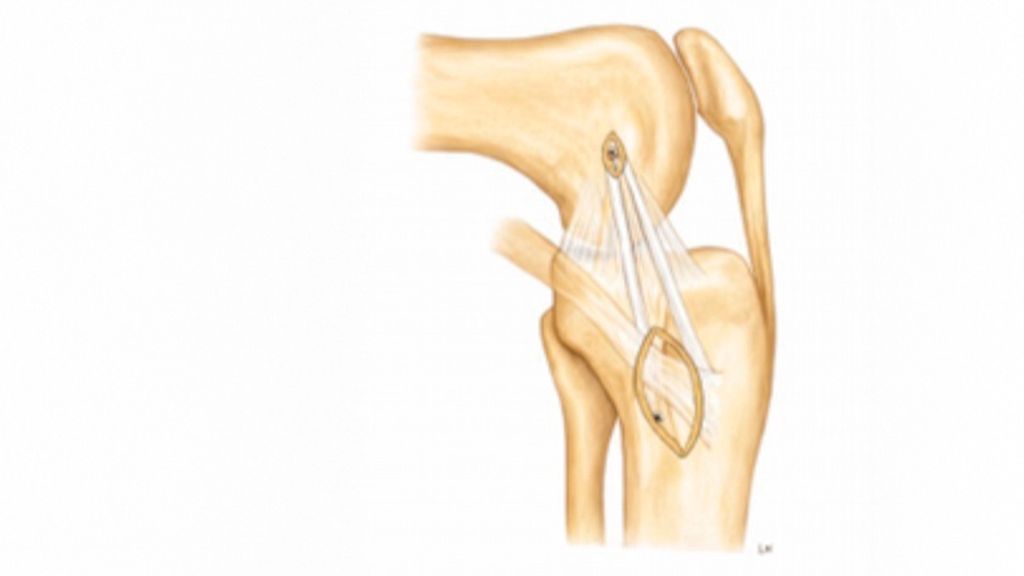

Kombinierte Verletzungen des medialen Kollateral- (MCL) und des vorderen Kreuzbandes (VKB) zählen zu den häufigsten multiligamentären Knieverletzungen. Bei vermeintlich isolierten VKB-Rupturen werden MCL-Verletzungen häufig unterschätzt bzw. nicht diagnostiziert. Dadurch kommt es nach VKB-Rekonstruktion und medialer Instabilität zu vermehrten VKB-Rerupturen. Eine optimale Therapie der anteromedialen Rotationsinstabilität (AMRI) erfordert daher eine detaillierte Diagnostik.

Isolierte oder kombinierte Verletzungen des medialen Kollateralbandes sind häufig. Zunehmende Evidenz zeigt, dass eine residuelle MCL-Laxität zu nachfolgenden Meniskus- und Knorpelschäden sowie zu einer erhöhten Belastung des VKB bzw. der VKB-Plastik führen kann, was wiederum das Risiko für eine VKB-Reruptur erhöht. Die aktuellen Therapiestrategien der AMRI variieren und umfassen sowohl operative als auch konservative Behandlungsansätze. Ein Konsens hinsichtlich Diagnostik, Klassifikation und Therapie der AMRI fehlt bislang aufgrund der begrenzten klinischen Studienlage.